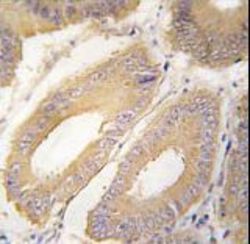

- Formalin-fixed and paraffin-embedded human colon carcinoma tissue reacted with FGF4 Antibody , which was peroxidase-conjugated to the secondary antibody, followed by DAB staining. This data demonstrates the use of this antibody for immunohistochemistry; clinical relevance has not been evaluated.

- Formalin-fixed and paraffin-embedded human colon carcinoma tissue reacted with FGF4 Antibody , which was peroxidase-conjugated to the secondary antibody, followed by DAB staining. This data demonstrates the use of this antibody for immunohistochemistry; clinical relevance has not been evaluated.

- Formalin-fixed and paraffin-embedded human colon carcinoma tissue reacted with FGF4 Antibody , which was peroxidase-conjugated to the secondary antibody, followed by DAB staining. This data demonstrates the use of this antibody for immunohistochemistry; clinical relevance has not been evaluated.